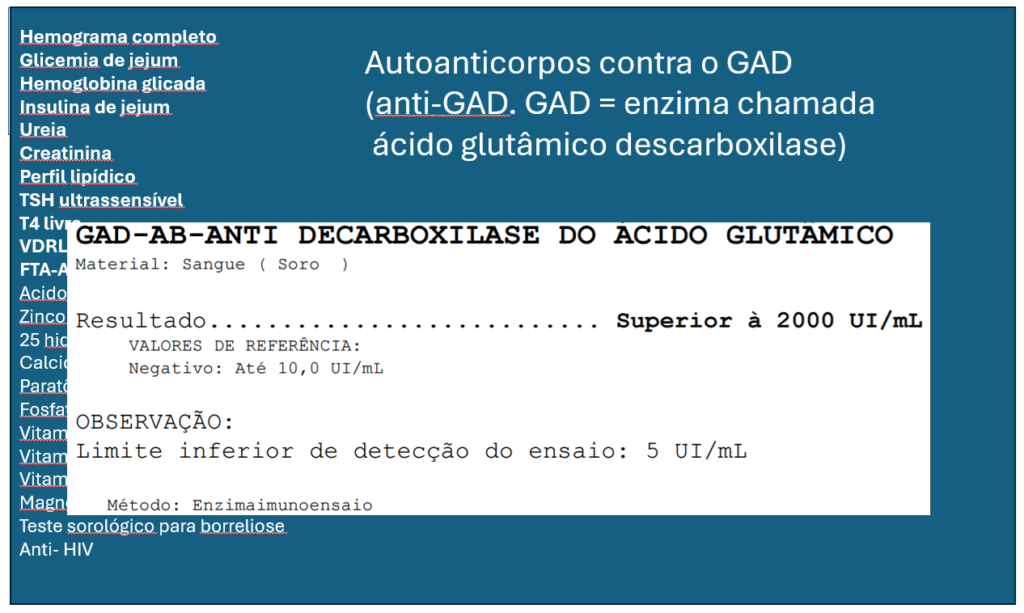

– Painel genético para ataxia espinocerebelar, dosagem de vitamina b12, b6, b1, magnésio, vitamina E, Anti Gad, ca 15.3, 19.9, 125, CEA, desidrogenase lática total, creatinoquinase total, complemento c3, c4, FAN, Anca (Anti citoplasma de neutrófilo c,p) e teste sorológico para borreliose.

O resultado foi positivo na dosagem do Anti-GAD.

Anticorpo anti-GAD associados ao NVI está como causa inflamatoria ou autoimune.

Autoanticorpos contra o GAD (GAD = ENZIMA chamada acido glutâmico descarboxilase.

A enzima ácido glutâmico dexcarboxilase (GAD) é a enzima que catalisa a conversão do ácido glutâmico em ácido gama-amino butírico (GABA), um neurotransmissor inibitório. Anticorpos contra GAD (anti-GAD-Ab) estão associados a uma variedade de condições neurológicas autoimunes, como síndrome da pessoa rígida, ataxia cerebelar, epilepsia e encefalite límbica. O espectro clínico da ataxia associada com anti-GAD-Ab abrange a síndrome de ataxia cerebelar progressiva lentamente, evoluindo em meses ou anos, associada à atrofia cerebelar na ressonância magnética cerebral. Há poucos relatos de pacientes com ataxia associada com anti-GAD-Ab apresentando movimentos oculares anormais, como NEVI.